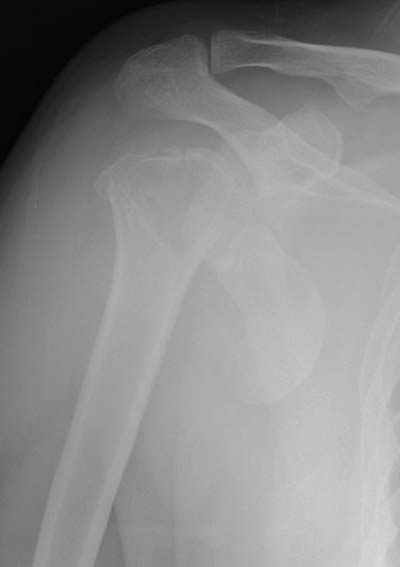

Спасибо за участие в дискуссии -перелом шейки плеча, для себя я прояснил многие технические моменты...

Посылаю послеоперационные Рг граммы.

Поздравляю, получилось просто замечательно. Если можно, расскажи чуть подробнее, как делали - как вправляли, как вводили спицы, поворачивали ли их?

Спасибо за поздравления:-))

Я и сам доволен результатом. В предпоследнем письме я кратко описал ход операции - закрыто репонировать не удалось( 2 недели с момента травмы и 1 неделя после неудачной репозиции) после удаления пучков спиц, пришлось сделать - 2см разрез на уровне перелома и с помощью периостального элеватора (золотое правило механики) *одеть* головку на дистальный отломок.

Спицы проводил через старые отверстия, вращая пучок импактором- направителем при его введении в головку.